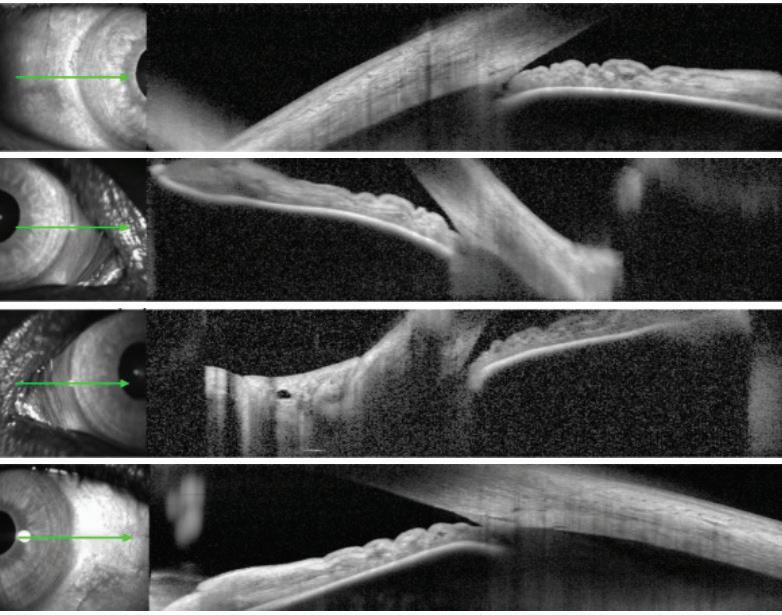

Ocular dialysis disequilibrium describes a proposed phenomenon whereby intraocular pressure increases during hemodialysis due to disproportionate changes in the osmolality of aqueous humor as opposed to the blood. This imbalance in osmolality is thought to disrupt the equilibrium between production and outflow of aqueous humor in the eye, which determines the intraocular pressure (IOP) (1). Elevations in intraocular pressure can lead to visionthreatening complications such as acute angle closure glaucoma, both in patients with existing glaucoma and those without. Furthermore, other risk factors or acute conditions can contribute to IOP elevations and may also need to be controlled. In the case presented below, a pars plana vitrectomy (PPV) and intraocular lens (IOL) exchange complicated by hyphema and vitreous hemorrhage likely exacerbated the issue,

as both can lead to increased ocular inflammation with blockage of the trabecular meshwork. This case presents an interesting etiology and potential solution for intraocular pressure elevation in an end-stage renal disease (ESRD) patient undergoing hemodialysis.

Case Presentation

A 74-year-old male presented for partially dislocated posterior chamber intraocular lens (PCIOL) in his left eye, which was his only functional eye. He suffered from multiple chronic illnesses, including Merkel cell carcinoma of the right eyelid and right parotid gland (currently in remission), blindness of the right eye due to complications from radiation treatments, chronic obstructive pulmonary disease, atrial fibrillation, gastroesophageal reflux disease, obstructive sleep apnea, coronary artery disease, and ESRD treated with dialysis for several years. Of note, the patient had not had any previous glaucoma or ocular hypertension issues. He subsequently underwent uncomplicated pars plana vitrectomy with IOL exchange with a scleral sutured IOL in the left eye. One day postoperatively the patient had a visual acuity of 20/40, but by day 3 post-operation, his vision had declined. One week post-operation, the patient’s vision was restricted to perception of hand motion only (HMO) with severe pain, and significant vitreous hemorrhage, hyphema, and small nasal choroidal effusion noted on examination. His measured intraocular pressure was 39 mmHg, far exceeding the generally accepted “normal” range of 10 to 21 mmHg. We were able to regain control of the IOP with administration of topical brimonidine, dorzolamide, timolol, Xalatan®, and oral Diamox®. With the patient’s IOP acutely managed, the plan at that time was to observe in the outpatient setting for spontaneous resolution of the previously noted hyphema and vitreous hemorrhage. However, during this observational period, he returned several times for urgent appointments due to severe pain,

in addition to nausea and vomiting. At this time, he was noted to have severe IOP elevations, with maximum recorded IOP reaching 53 mmHg. Given the unclear etiology of the patient’s symptoms, he was admitted to the hospital for pain control and very close observation. Over the course of his inpatient stay, his IOP was checked frequently and noted to only severely spike in the evenings after dialysis. He was evaluated multiple times while on dialysis and never had significant elevation of IOP during treatment itself. At that time, we surmised that fluid shifts were a possible etiology of his symptoms, especially with vitreous humor now absent post PPV. Lengthy discussions with nephrology led to a plan to prolong dialysis treatment times, running the dialysis machine as slowly as possible to hopefully slow electrolyte and fluid shifts into the eye, with the goal of stopping the IOP spikes following dialysis sessions. The patient responded very well to this modified, prolonged dialysis protocol. His IOP never exceeded 24 mmHg and was typically in the middle to upper teens. Furthermore, with the addition of a fourth dialysis day per week, his IOP has been in the middle teens, even with discontinuation of Diamox. We have observed consistent IOP maintenance for months on this regimen. The patient additionally underwent anterior and posterior chamber wash out to treat his persistent vitreous hemorrhage. He is currently doing very well and seeing well from the previously affected eye. He has not had any significant IOP elevations since the alteration of his dialysis protocol.

Discussion